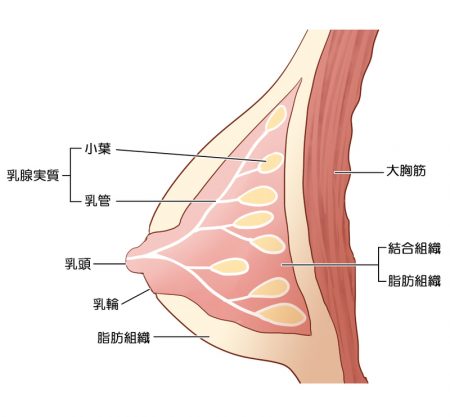

高濃度乳房とは

乳房は主に脂肪と乳腺実質(小葉、乳管)からできています。

高濃度乳房を一言で言うと、

乳腺実質の割合が多い乳房のこと。

英語では、Dense Breastと呼びます。